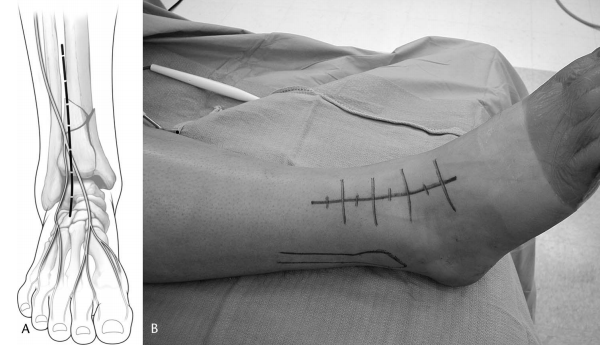

一旦处理了腓骨骨折,如前所述,前外侧切口以踝关节为中心,远端平行于第四跖骨,近端位于胫骨和腓骨之间(图 1)。切口近端延伸超过踝关节 7 厘米以上会破坏前间室肌肉的起点。远端,切口终止于距舟关节稍远侧。需要切口的远端范围来直视穹顶后部和应用通用撑开器。

图 1. (A) 示意图和 (B) 临床照片,显示扩大前外侧显露的切口,以踝关节为中心,远端平行于第四跖骨,近端位于胫骨和腓骨之间。